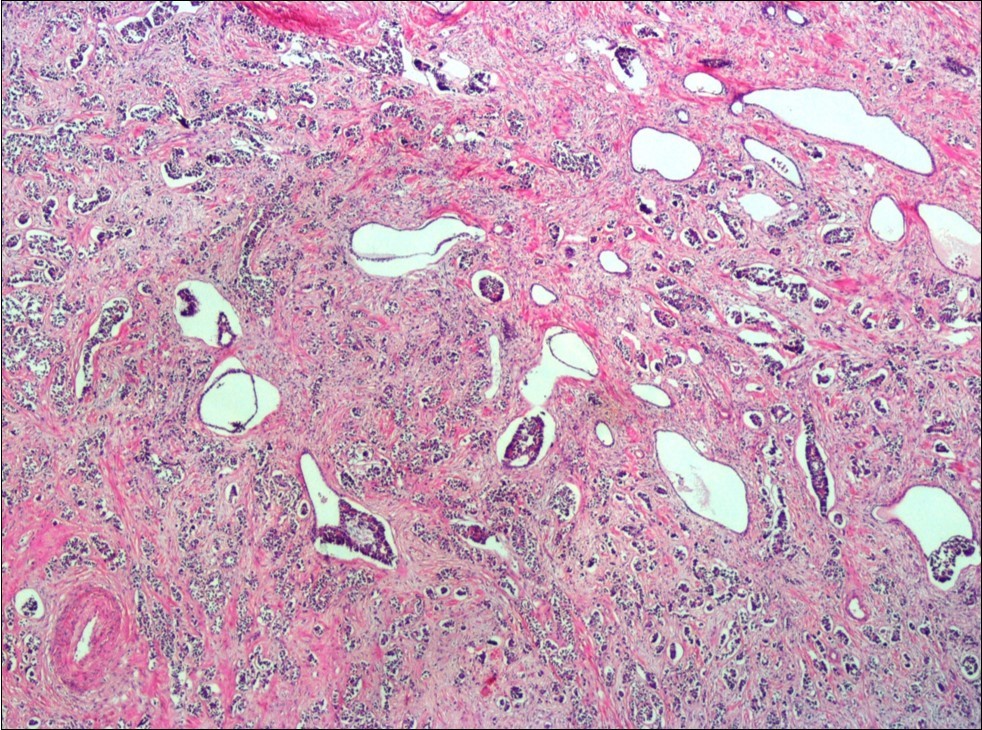

A 73-year-old male patient was admitted to our outpatient clinic with acute urinary retention. Digital rectal examination was normal. The PSA value was 1.81 ng/dl. Prostate size was 101 cc. Since the PSA value and digital rectal examination were normal, no biopsy was taken. Ultrasonography showed bilaterally ureterohydronephrosis. The creatinine level was 2.89 mg/dl. Hypertension has been presented as a comorbidity. An 18 Fr Foley catheter was inserted and alpha-blockers and 5-α reductase inhibitor medication was given. Creatinine level decreased to 0.91 mg/dl after one week. When the patient's catheter was pulled out, he could not urinate again. A catheter was inserted and waited one week more. After one week, the patient was unable to urinate again. The operation was decided due to this recurrent urinary retention. Because of prostate size was 101 cc and prostatic urethra was long, open prostatectomy was decided. When the prostate was removed during the operation, it was evaluated that the left side and the lower side were adhered to surrounding tissue. The prostate was removed as an en bloc. The catheter was removed after 5 days. The pathology of the patient has been reported as pure small cell prostate carcinoma. On the microscopic examination, the tumor was heavily infiltrated into the prostate parenchyma (Figure 1). Tumor cells were consist of atypical small-medium sized, mitotically active cells with a high nuclear to cytoplasmic ratio, hyperchromatic nucleus, nuclear molding, and inconspicuous nucleoli (Figure 2). On the immunohistochemically examination of synaptophysin showed diffusely and strong positivity while chromogranin A showed focal weak positivity with the absence of staining for PSA (Figure 3). Ki67 proliferative index was equal to 90% of the tumor cells (Figure 4). The results confirmed the diagnosis of prostatic small cell carcinoma. Metastatic lymph nodes were detected in the right perirectal region with metastatic multiple lymph nodes in the bilateral external iliac region, more on the left than in the PET CT. No metastasis was detected in the brain MRI and thorax computed tomography. Four cycles of etoposide and cisplatin chemotherapy were administered to the patient. Control PET CT taken after chemotherapy showed a significant decrease in size and metabolic activity of the right obturator and lymph nodes in the right perirectal area. The size and metabolic character of the left obturator, left external iliac and common iliac lymph nodes were increased. After a month, patient admitted to emergency outpatient clinic with left flank pain. There was an 8-cm mass in retroperitoneal area in the computed tomography. Supportive treatment was started because the patient could not tolerate chemotherapy. The masses reached to 13x11cm and fulfilled the retroperitoneal area. Multiple lung metastases were seen. The patient died 13 months later after the first diagnosis.

Figure 1.Infiltration of the tumor cells between prostatic ducts (H&E, x40)